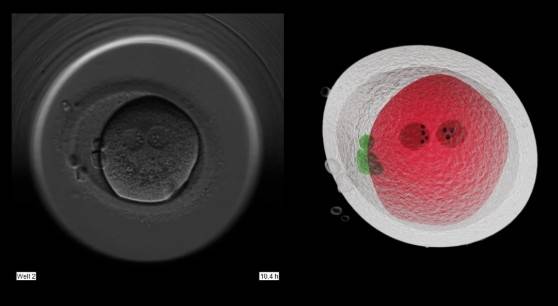

![정자·난자를 수정한 배아 촬영 현미경 이미지(왼쪽)와 3차원 분석 사진. 싱가포르 난임 클리닉인 젠프라임은 배아 구조와 발달 상태를 입체적으로 분석한 데이터를 바탕으로 인공지능이 직접 착상 가능성이 가장 높은 배아를 선별한다. [젠프라임]](https://img1.daumcdn.net/thumb/R658x0.q70/?fname=https://t1.daumcdn.net/news/202512/31/mk/20251231175704892uzbm.jpg)

젠프라임은 인공지능(AI)을 활용해 10여 개 배아의 세포 분열 속도와 형태적 안정성을 정밀 분석한 뒤, 착상 가능성이 가장 높은 배아를 찾아낸다.

AI의 도움을 받은 시술의 임신 성공률은 무려 78%(30세 미만 기준)에 육박한다. 종전 기술로는 난임 시술을 통한 임신 성공률이 평균 36.9%(2022년 한국 체외수정 기준)에 그친다.